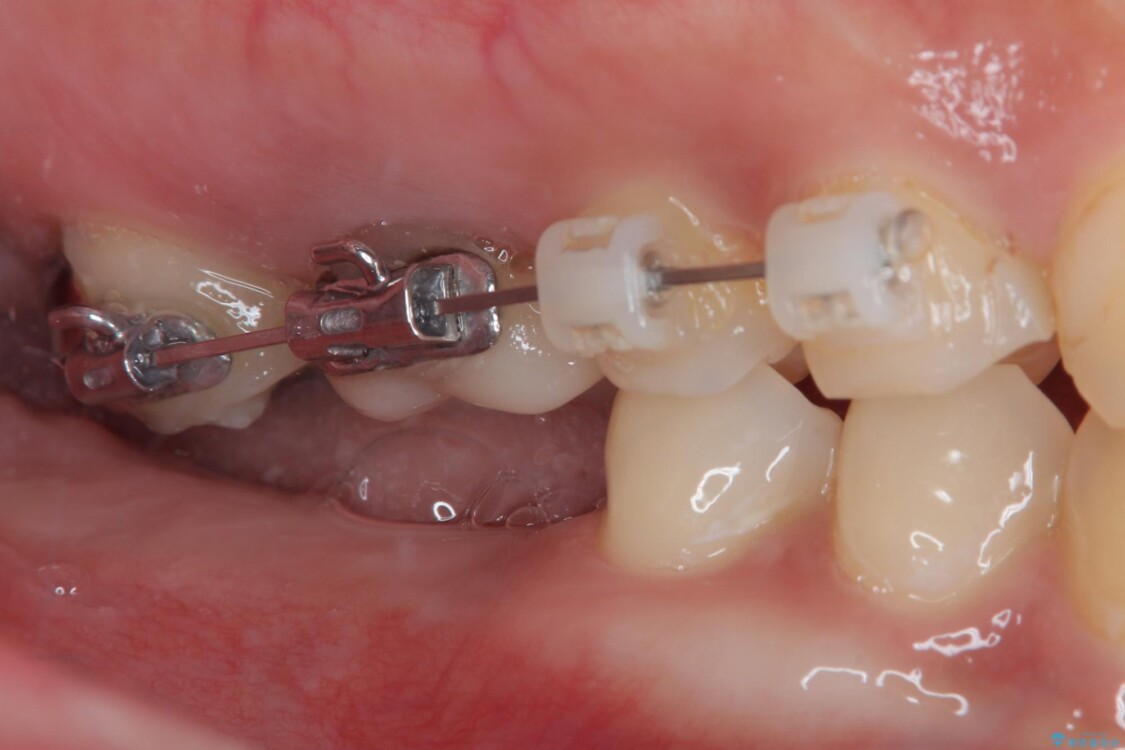

そこで、右上の奥歯に部分的なワイヤーを装着し、さらに矯正用アンカースクリュー(TADs)を併用することで、挺出した歯を圧下(歯を元の高さに戻す動き)させ、下顎にインプラントを埋入するための十分な垂直的スペースを確保しました。

→ この装置は部分的な矯正で、前歯など見える位置にワイヤーがかかることはなく、見た目を気にすることなく、普段通りの生活を送りながら治療を進めることができました。

• 挺出歯を圧下してスペースを確保!目立たない部分矯正で下顎大臼歯にインプラント治療を実現 治療途中画像